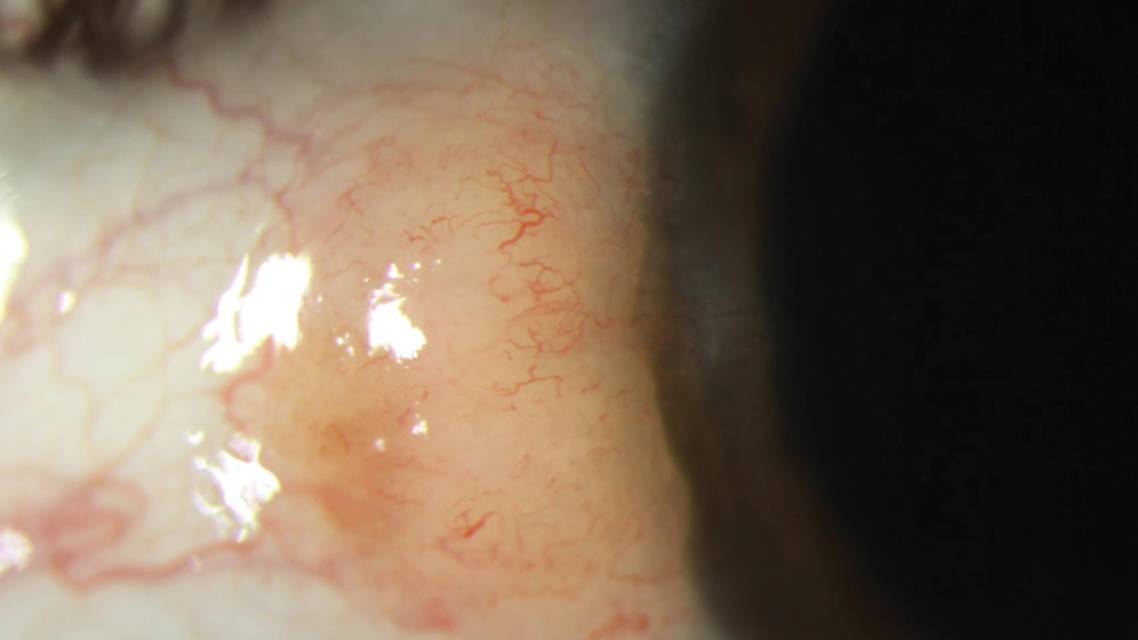

A 56-year-old female presented for evaluation of dryness associated with a persistently injected pterygium. Examination revealed suspicious features, including a mild gelatinous papillary appearance and a feeder vessel. I performed HR-OCT to better evaluate the lesion. The systematic approach aided with diagnosis (Figure 2).

1. Find the base of the epithelium.

2. Assess the main lesion. Is it epithelial or subepithelial? (Epithelial.)

3. Determine whether an abrupt transition exists. (Yes, there is an abrupt transition from normal to abnormal epithelium.)

4. Is the epithelium hyperreflective? Thickened? (Hyperreflective, and the epithelium appears thickened.)

The answers to these questions corresponded with the three classic features of conjunctival ocular surface squamous neoplasia (OSSN) seen on HR-OCT2,4: 1) Thickened epithelium, 2) strongly hyperreflective epithelium, 3) usually with an abrupt transition from normal to abnormal epithelium. The subepithelial layer is usually not involved. The main difference between OSSN and pterygium is the location of the lesion (epithelial for OSSN, subepithelial for pterygium), and other morphologic features (Table). In studies using the commercially available RTVue, an epithelial thickness of 120 µm to 140 µm was considered highly sensitive and specific for OSSN.5 However, the optimal numeric epithelial thickness cutoff for each device remains unknown, and all data should be considered within the clinical scenario.2